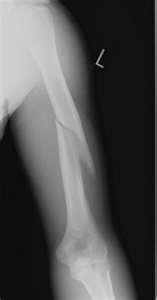

| Broken Humerus |

My 10-year-old daughter was a casualty of a playground structure. She fell over 7 feet, hitting a piece of equipment on the way down and snapped her humerus. That’s the big bone in the upper arm. The worst part? It was preventable. SafeKidsUSA and CastCoverz! wants all parents, educators, and playground supervisor’s to be aware of school playground dangers. But, we also want you to know that most accidents are preventable. Our next post will be about the ways school playground accidents can be prevented. In the meantime, have fun with your friends, study hard, and BE SAFE!